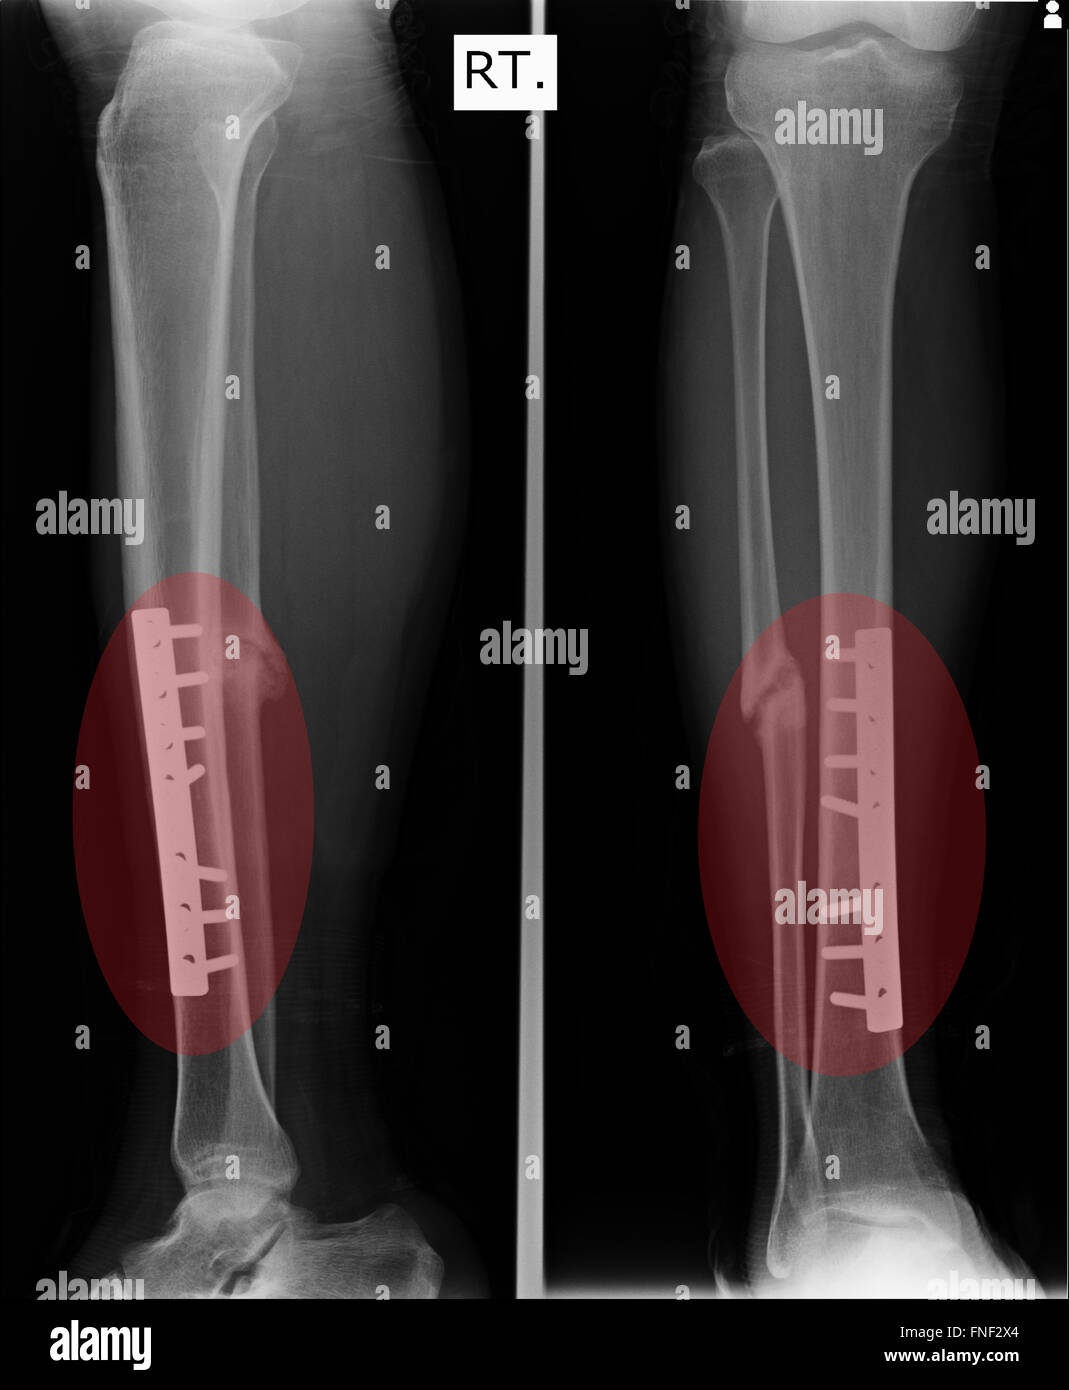

Figure 5 from Small fragment locking plate as provisional internal fixation in severe open both